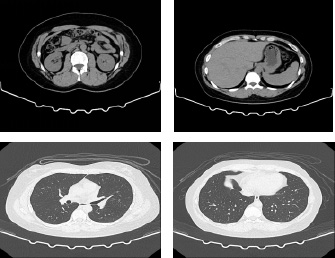

CT装置

- ・輪切りや色々な角度の3D 画像で人体の中を撮影出来ます。

- ・健診~精密検査まで幅広く使用します。